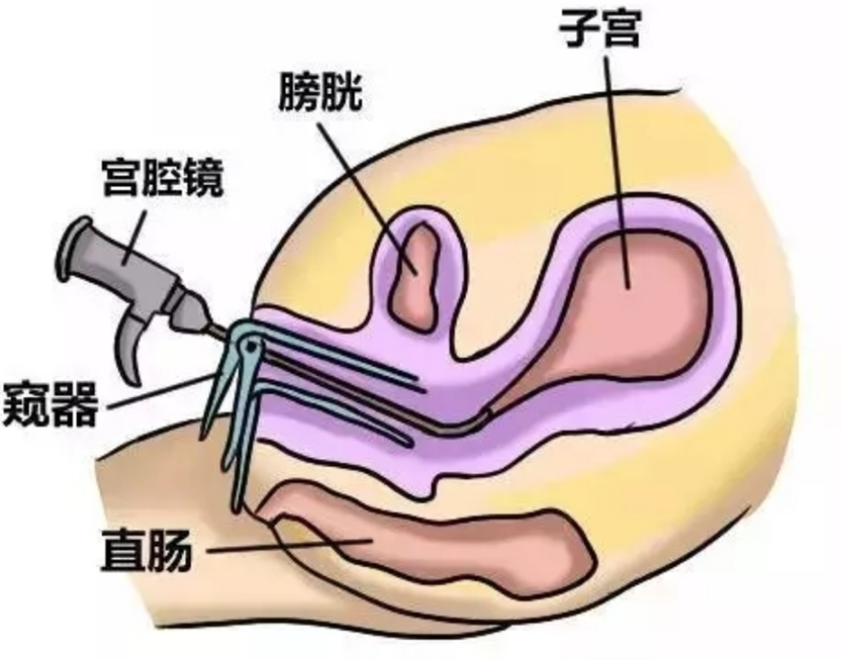

人工陰道治療中的

人工陰道作用

人工陰道治療

人工陰道治療前期

人工陰道治療前後

A:原發性陰道鱗狀上皮癌對放療比較敏感,可採用腔內鐳療、體外照射或放射性同位素局部應用等治療。一般早期陰道癌以腔內照射為主,放射源主要為鐳及鈷,現在多用銫,利用陰道容器,裝配不同劑量及放置不同時間。體外照射治療時放射量由主治醫師根據患者情況具體……

A:陰道癌就是指陰道內出現有惡性腫瘤。常見的陰道癌包括陰道腺癌、陰道基底細胞癌,以及陰道肉瘤或者疣狀癌等。而陰道癌常常是在陰道的側壁出現菜花樣贅生物,伴有血性的滲出分泌物流出,而且常常會有明顯的疼痛表現。主要的檢查手段就是需要做陰道鏡下的陰道壁……